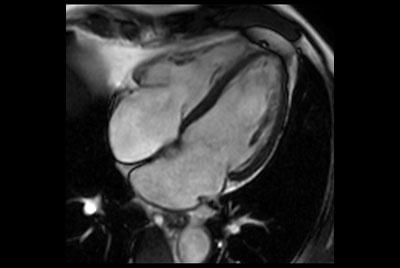

Myocardial infarction with T1/T2 Mapping